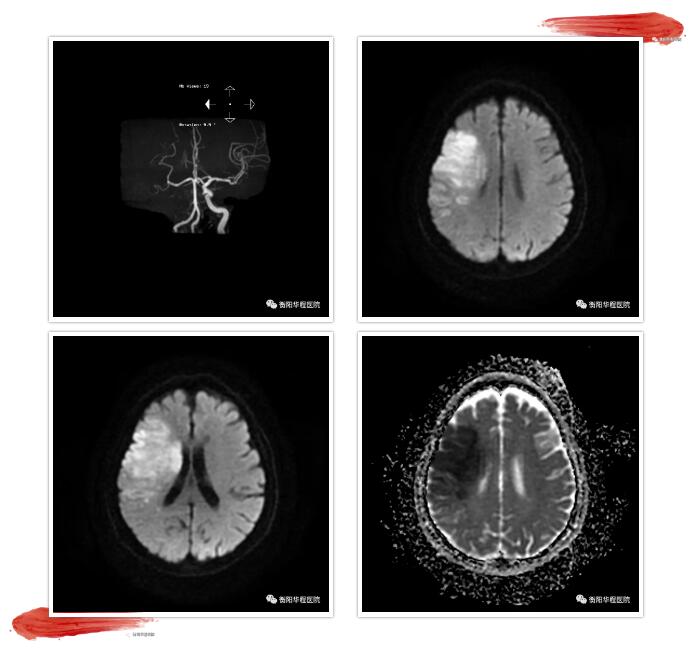

此刻,時(shí)間就是大腦,從接診病人、問病史、體格檢查、完善相關(guān)檢查、談話溝通交待病情到開始靜脈注射阿替普酶只用了短短15分鐘。溶栓治療后該患者在我科搶救病房施行持續(xù)神經(jīng)重癥監(jiān)護(hù),入院第二天完善頭部MRI+DWI+MRA+SWI可見顱內(nèi)梗死病灶范圍散在,且未見微出血病灶,證實(shí)此次溶栓治療安全有效。該例急性腦梗死患者,是我院我科使用阿替普酶靜脈溶栓第一例,也是我院急診科及我科醫(yī)護(hù)人員奮力為急性腦卒中患者開通生命綠色通道的努力成果。